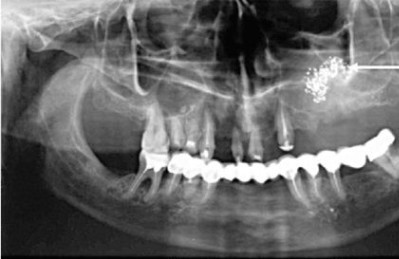

Воспалительное заболевание гайморовой пазухи, чаще с одной стороны, возникшее вследствие распространения инфекционно-воспалительного процесса с пораженных зубов верхней челюсти называется одонтогенным гайморитом.

Это происходит достаточно часто – в 10-12% всех случаев гайморита – благодаря анатомической особенности соотношения гайморовых пазух и зубов верхней челюсти.

Корни зубов верхней челюсти находятся в альвеолярных отростках и в некоторых местах очень близко располагаются к полости гайморовой пазухи. Это «слабое» место, где, при нарушении тонкого барьера, микроорганизмы из полости рта могут попадать в синус верхней челюсти и вызывать патологический процесс.

Довольно частая анатомическая особенность, когда корень зуба расположен глубоко верхней челюсти – в нижней стенке гайморовой пазухи, где он может находиться практически под мембраной Шнайдера.

В некоторых случаях толщина костной стенки между слизистой оболочкой и корнем составляет менее 1 мм. В таком случае любой воспалительный процесс в верхушке корня может послужить причиной гайморита.

Одним из самых распространенных, «безобидных» на первый взгляд, но очень серьезных заболеваний зубов является кариес – поражение происходит по самый корень и после влечет за собой воспаление. Периодонтиты, кисты и пародонтиты способствуют истончению костной стенки альвеолярного отростка верхней челюсти.

Данная анатомическая особенность выявляется с помощью рентгенологического исследования. Если она присутствует, нужно уделять особое внимание гигиене полости рта для профилактики заболевания.